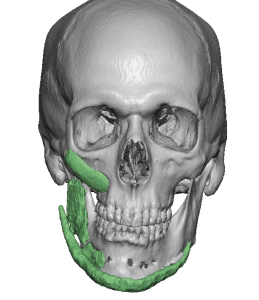

Custom designed or 3D jaw implants are the contemporary workhorse in lower facial asymmetry corrections. With modern patient-specific CT-based implant designing virtual planning an be done to design different right and left dimensions, matching the right and left sides of the jawline and centering the chain can be done far more accurately than stock implants ever could. 3D imaging is important because facial asymmetry is a true 3D problem and standard 2D assessment, even with plain x-rays and 2D CT scans, can not fully appreciate the extent of the asymmetries down to the millimeter level.

In treating secondary facial asymmetries in which a 2D approach has been taken to the mplant used and their placement it can be very much an historical adventure. The implants used and their position is known beforehand by the 3D CT scan but unearthing them and digging them out poses it own set of challenges in many cases.

- Secondary facial asymmetry surgery will run into prior implant placements and osteotomy fixation hardware which must be considered in the treatment planning.

- Most jaw asymmetries are best treated by a wrap around jawline implant approach to manage the bilateral deformities.